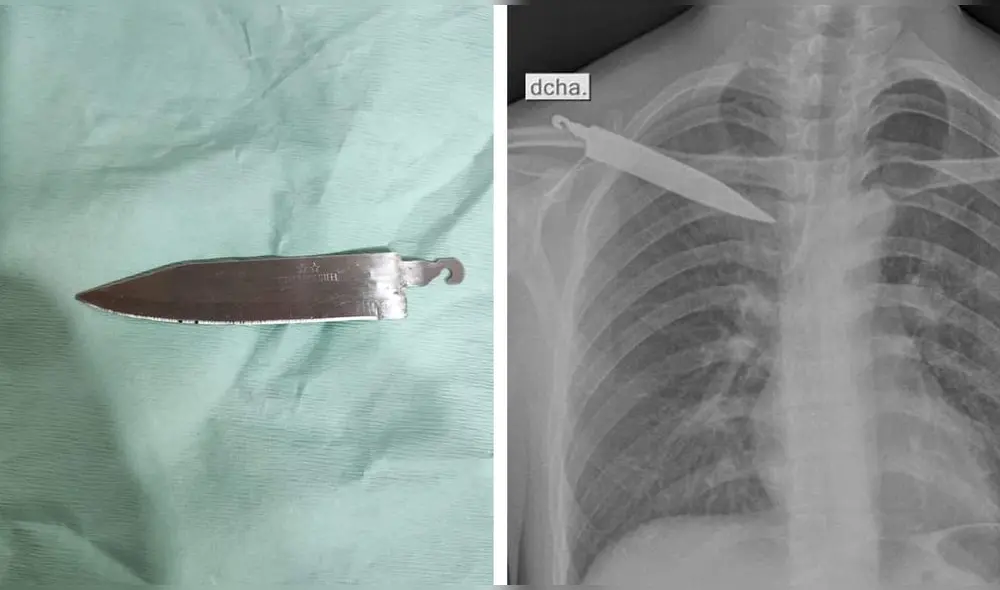

Un joven ingresó a un centro de salud en el distrito de Pangoa, Junín, por un dolor de espalda, y el médico indicó que era necesario realizar un examen de rayos X. Tras realizarse las pruebas correspondientes, se determinó que Gerson Tarazona Gálvez (28) tenía un cuchillo introducido en esa parte de su cuerpo. Inmediatamente, el objeto fue extraído después de una intervención quirúrgica.

Tarazona Gálvez manifestó que hace un mes sufrió un robo en Huánuco y se trasladó a un hospital de esa ciudad donde solo le saturaron la herida y no se dieron cuenta del objeto incrustado. Desde entonces el dolor no paró. Posteriormente, el joven realizó un viaje a Junín para visitar a su tía e indicó a sus familiares que le dolía mucho la espalda y esto le impedía trabajar.

La Dirección Regional de Salud Junín señaló que el joven intentó defenderse de los malhechores. La operación en la que se extrajo el objeto fue en el Hospital de Pangoa y cinco profesionales estuvieron a cargo de la intervención.